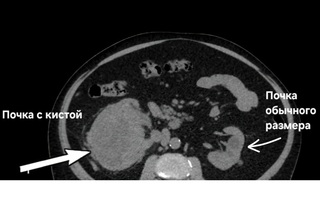

«В урологическое отделение БГКБ поступил 63-летний житель Балаково. О наличии у себя кисты почки мужчина знал давно, но от оперативного лечения отказывался, предпочитая просто «наблюдать». Со временем ситуация осложнилась мочекаменной болезнью. После попытки лечения в другом городе у пациента развилось тяжелое осложнение — инфицирование кисты.

Когда пациент поступил в стационар городской больницы, его состояние было критическим. Киста превратилась в огромный очаг воспаления. В ходе экстренной операции врачи дренировали из почки 400 миллилитров инфицированной жидкости.